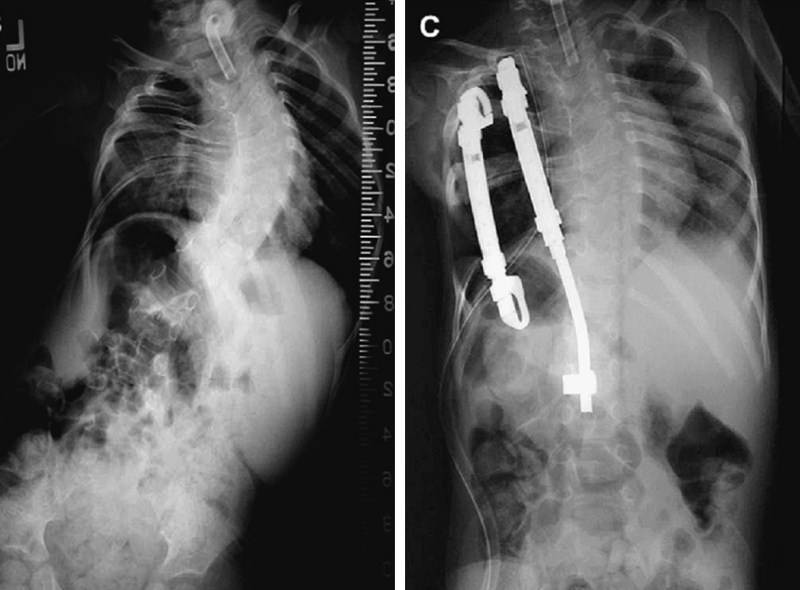

目前,生长棒作为非融合技术治疗EOS已被国内外学者认可,其适于畸形进展迅速、支具控制不佳者,理想手术年龄为6-9岁,至12-14岁行终末融合。

图3 6岁EOIS患儿,术前冠状面全脊柱正位X片(左),采用双生长棒技术,两端固定,顶椎撑开,术后6月复查正位X片(右)